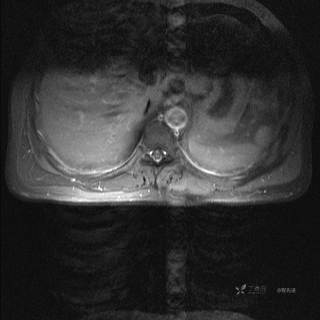

MR

T1增强冠状位

T1增强横断位